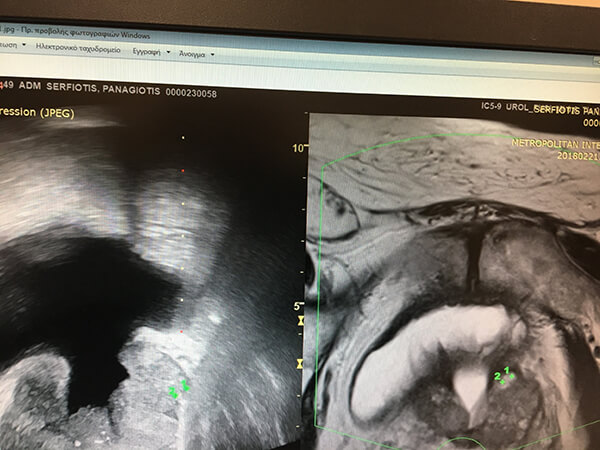

Ηλικιωμένος άνδρας με διουρηθρική προστατεκτομή.

Δεξιά: εικόνα μαγνητικής τομογραφίας στην οποία έχουμε μαρκάρει την ύποπτη εστία.

Αριστερά: αντίστοιχη υπερηχογραφική εικόνα στην οποία, ενώ δεν φαίνεται η εστία, φαίνονται το μαρκάρισμα και η βελόνα βιοψίας που κατευθύνεται προς τον στόχο.